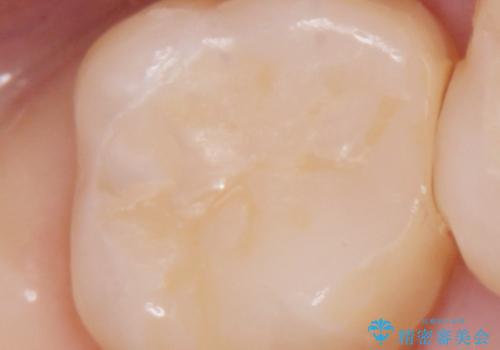

拡大鏡下で詰め物を外し、う蝕がない事を確認して、セラミック(e-maxインレー)で治療を行いました。

セラミックの詰め物(e-maxインレー)は歯質との隙間ができにくく

虫歯の再発リスクが低くなります。

口を開けた時、銀歯が目立たなくなり、大変満足して頂けました。